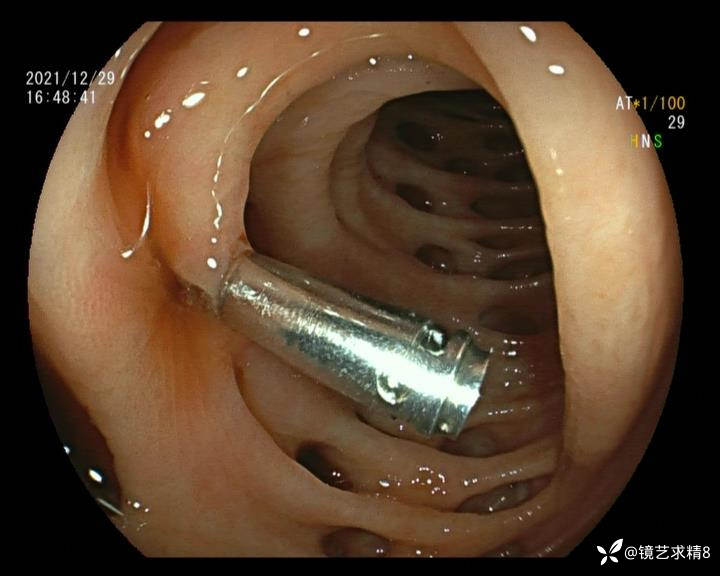

患者以消化道出血入院,胃镜未见异常,肠镜进入乙状结肠就看到很多憩室,同时还看到肠腔用清肠药后移动下来1枚尖锐的枣核,这么多憩室,这个枣核扎入憩室的机会非常大,推测应该是掉入一坑🕳就算出来还会有很多坑🕳🕳🕳等着,掉入憩室内很容易刺破血管,这可能就是消化道出血的原因,继续前进可以看到有一些憩室内翻,还有一些息肉,问题来了,那么多憩室,犯罪分子是抓住了,它在那些憩室内作过案?到达回盲部后挨个冲洗,但憩室大小又不足以把镜头进入憩室内观察,针对有血块的憩室冲洗后可疑出血的以夹子闭合或套扎,取出枣核,如果有锥形透明帽可能钻入憩室精准电凝效果更好,若内镜下操作失败介入治疗成功率更高,经内镜下治疗后观察未再出血出院。